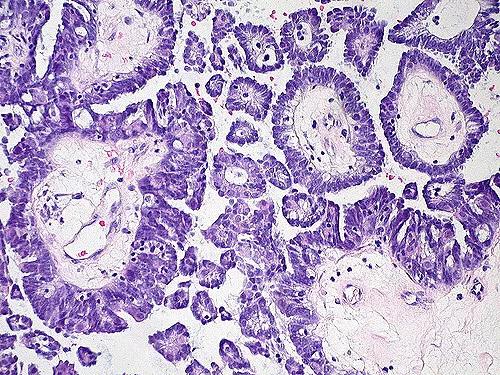

另一个方法是CT引导下穿刺活检。因为有时候在腹水里是找不到肿瘤细胞的,这种情况下需要在CT的监视下,在允许的可疑部位穿刺活检做病理。病理可能是这样的:

当然,不论是放腹水找瘤细胞,还是穿刺活检,都属于有创操作,是有风险的。需要综合评估权衡。